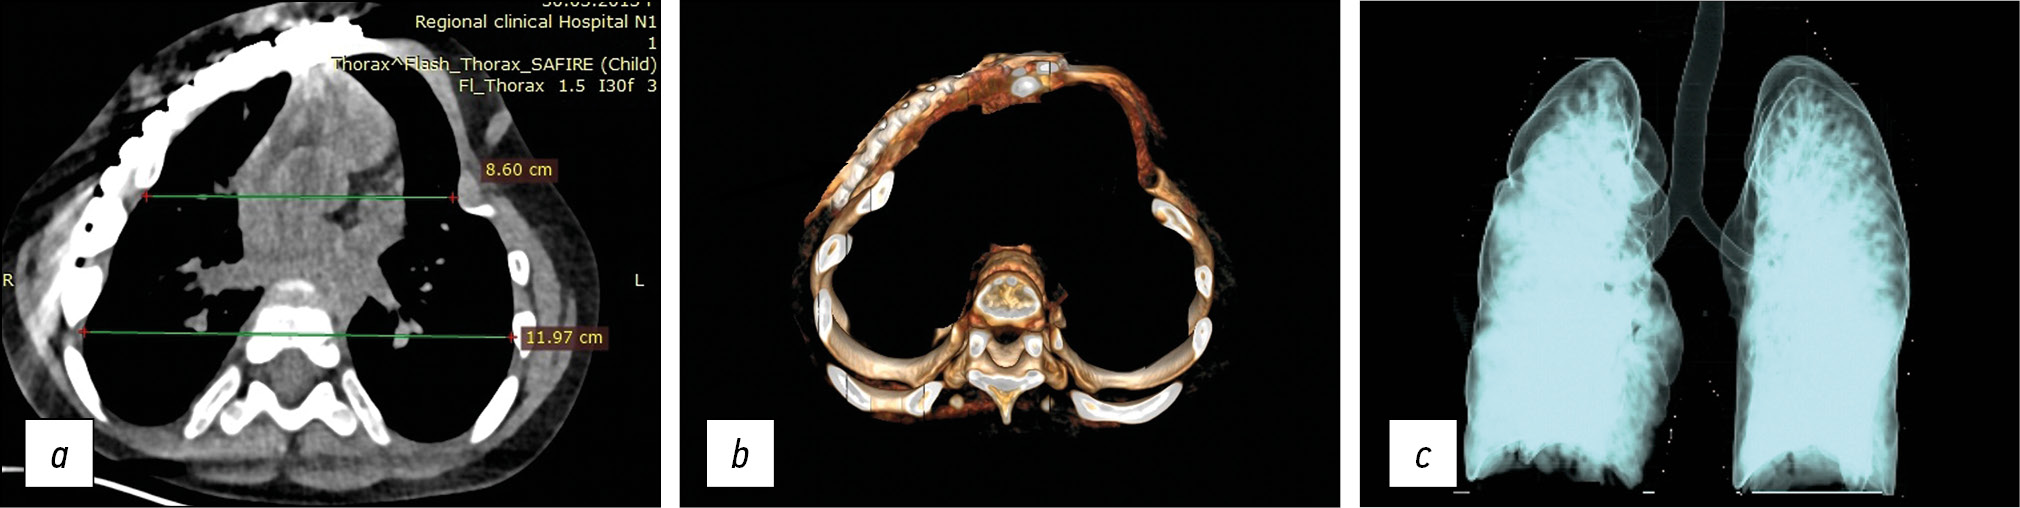

По данным КТ через 2 нед. после второго этапа операции оба гемиторакса имеют правильные контуры; ГРК фиксирован пластинами с обеих сторон в варианте «ребро–грудина». ИГКГК составил 86 %, при этом объем правого легкого увеличился в сравнении с исходным на 26,7 %, в то время как увеличения объема левого легкого не отмечено (табл. 2, рис. 4).

Рис. 4. Компьютерная томограмма (а) и 3D-компьютерная реконструкция (b, c) после II этапа реконструкции грудной клетки: а — аксиальный срез; b — положение одной из реберных пластин отмечено стрелкой; c — фронтальный вид; d — 3D-мультиобъемная реконструкция

Fig. 4. Axial sections of CT scan (a), 3D-CAT scan (b), frontal chest 3D-CAT (c), and lung 3D-MVR (d) after the II stage of the surgery (See the text for the details)

Таким образом, суммарное увеличение объема правого гемиторакса за период наблюдения составило 224,4 см3 или +36,3 % по сравнению с исходным, при этом показатель ИГКГК увеличился на 26 %, что составило +43,2 % по сравнению с исходным. Объяснением отсутствия увеличения объема левого легкого после реконструкции левого гемиторакса могут быть, с одной стороны, большая выраженность фиброзных изменений в нем ввиду более длительного существования компрессии, с другой — достаточно раннее (8-е сутки после операции) проведение КТ, что может быть недостаточным для адаптации легкого к новому объему гемиторакса.